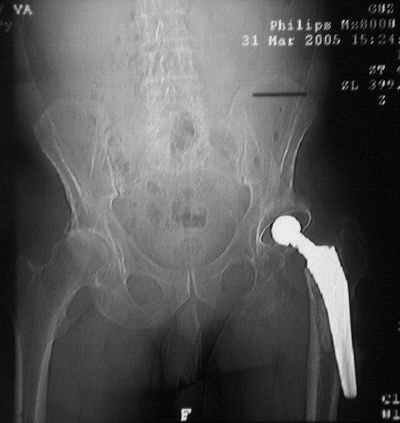

Уважаемые коллеги,Мужчина, 69 лет, в декабре 2004 г перенес тотальную цементную артропластику . Через 3 мес после операции на фоне прогрессирующих болей в средней и проксимальной третях бедра при нагрузке возникли резкие боли и появилось опухолевидное болезненно образование. Процесс сопровождался резким одномоментным укорочением ноги.

В феврале 2005 г. выполнена ревизионная артропластика, завершившаяся прогрессировавшим в течение 1-2 мес укорочением ноги. В настоящее время ходит только с костылями, при движениях в тазобедренном суставе испытывает резкие боли, ощущает хруст. Попытка осевой нагрузки бедра сопровождается ощущением "перемещения поршня" и заметным по внешним ориентирам укорочением левой ноги на 1-1,5 см.

Наверное перфорация стенки при первичном протезировании и неадекватный размер Вагнера при ревизионном? Что-нибудь еще?

Я полностью поддерживаю Ваше мнение об интраоперационной перфорации при первичном протезировании, т.к. при внимательном рассмотрении рентгенограммы после этого этапа виден дефект кортикального слоя именно по задне-наружной поверхности .

К сожалению, Р-граммы не захватывают полностью бедро, поэтому окончательное решение может быть после полноценного р-ского обследования. Однако думаю, что оптимальное решение - полнопокрытая ножка длинной не менее 200 мм, без привязки к типу протеза. Это может быть модульная система ZMR, Solution и др., главное - принцип. В отношении чашки тоже есть определенные сомнения. Думаю, что наш ин-т (РосНИИТО, СПб) смог бы сделать эту операцию.

Ситуация достаточно несложная. Основной массив бедренной кости сохранён. Лучше поменять чашку сразу, потому что ей не долго осталось жить. Слишком латерально поставлена. Предпочитаю RM чашки при ревизии. Ножка предпочтительней Solution. Если есть проблемы по замене, могу взять к себе без проблем.